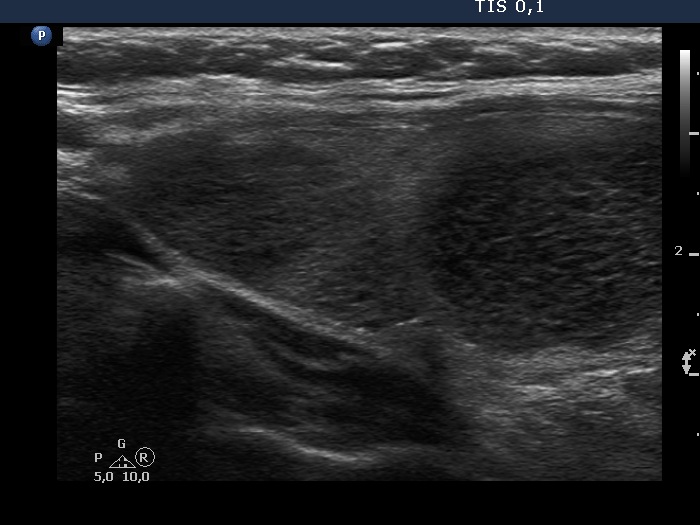

Second examination 3 years later (second, fourth and sixth rows of images):

Ultrasonography. Compared with the previous examination, both the number and the size of discrete lesions in the thyroid have increased.